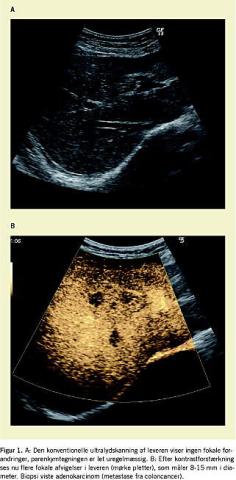

Sygehistorien omhandler en 67-årig kvinde med biopsiverificeret coloncancer. En blodprøve havde vist forhøjede leverenzymer, og der blev derfor rejst mistanke om levermetastaser. En konventionel (almindelig) abdominal US viste en normal stor lever med ganske let uregelmæssigt parenkymtegning, men ingen fokale forandringer (Figur 1A ). US blev nu gentaget efter en standarddosis af ultralydkontrastmidlet Sonovue (Bracco, Italien), der blev administreret intravenøst. Denne kontrastforstærkede US viste adskillige (ca. 10) fokale forandringer i begge leverlapper med et for metastaser typisk udvaskningsmønster under kontrastskanningen (Figur 1B ). Der blev foretaget finnåls-aspirationsbiopsi, som blev vejledt af den kontrastforstærkede US, og svaret fra patologerne viste adenokarcinom, der var foreneligt med metastase fra patientens coloncancer.